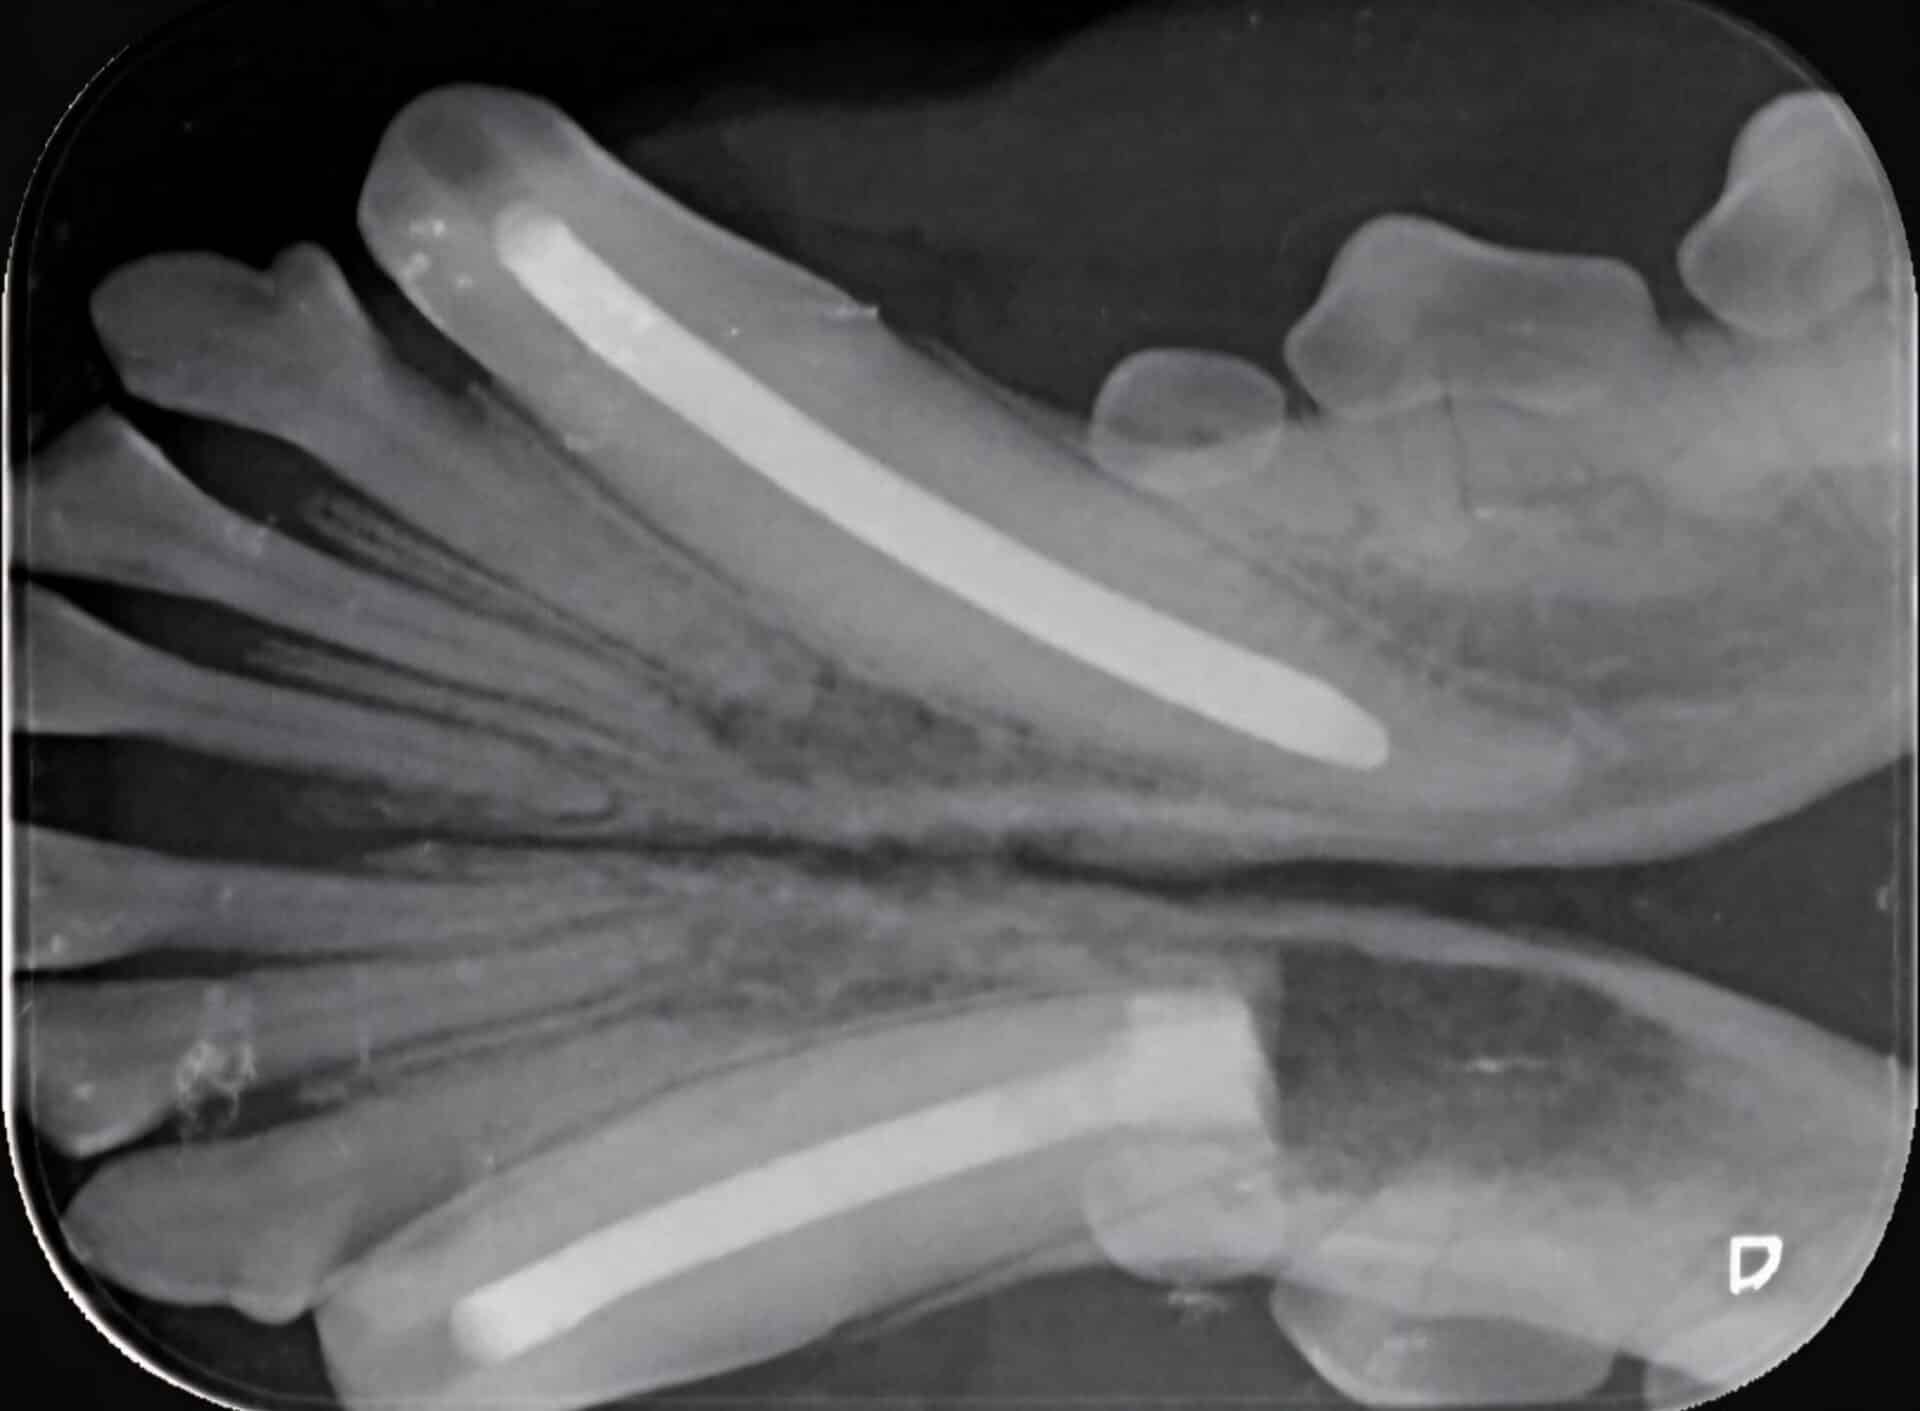

What Lies Beneath: Systemic Approach to Radiographic Interpretation (2-hour Live Dental CE event)

- Indications for dental radiographs

- Normal Radiographic anatomy

- Learn how to properly orientate dental images

- The systematic approach for radiographic interpretation

- Discuss cases and recommendations for treatment